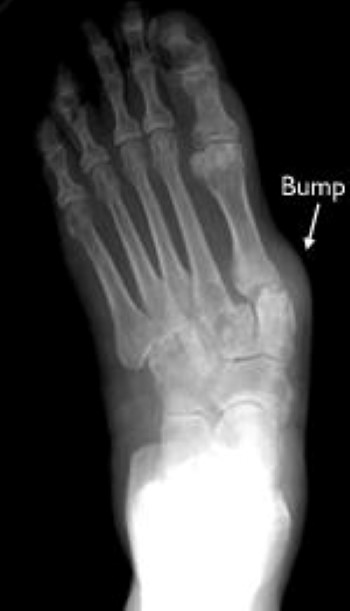

- Over time, the shape of the foot can change because the structures that support it degenerate. This can create a large bony prominence (bump) on the arch. All of these changes in the shape of the foot can make it very difficult to wear shoes.

Skin. The location of callouses indicate areas of abnormal pressure on the foot. The most common location is on the ball of the foot (the underside of the forefoot). If the middle of the foot is involved, there may be a large prominence (bump) on the inside and bottom of the foot. This can cause callouses.

X-rays. X-rays create images of dense structures, like bone, and they will show your doctor the position of the bones. The X-rays can be used by your doctor to make measurements of the alignment of the bones and joint spaces, which will help your doctor determine which surgery would be best.